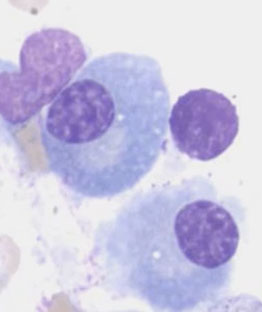

Indolent cancer of B-cells with "hairy" cytoplasmic projections, oval nuclei and lots of cytoplasm

PB: large lymph (double size of normal lymph) c round or reniform nuclei c smooth contours, ground glass chromatin c indistinct to absen nucleoli

can have circumferential hairy projections caused by frayed cytoplasmic edge

Cells look hairy b/c of overexpression of Rho family of small GTPases and Gas7 molecule up-regulation (a growth-arrest molecule)